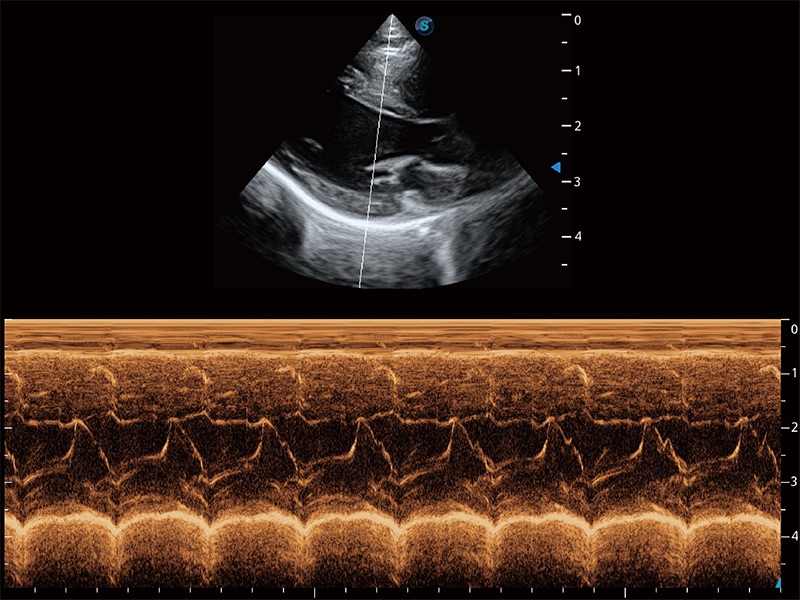

通過360度任意調(diào)節(jié)3條M型取樣線,在同一心動周期上觀察心臟不同位置的運(yùn)動曲線,得到準(zhǔn)確的心功能測量數(shù)據(jù),有效評估心肌運(yùn)動及左心室功能。

能夠基于左心室壁追蹤和辛普森法,自動計算射血分?jǐn)?shù),支持多個可移動點(diǎn)描跡,與手動測量相比,極大節(jié)省了動物醫(yī)生的時間和精力。